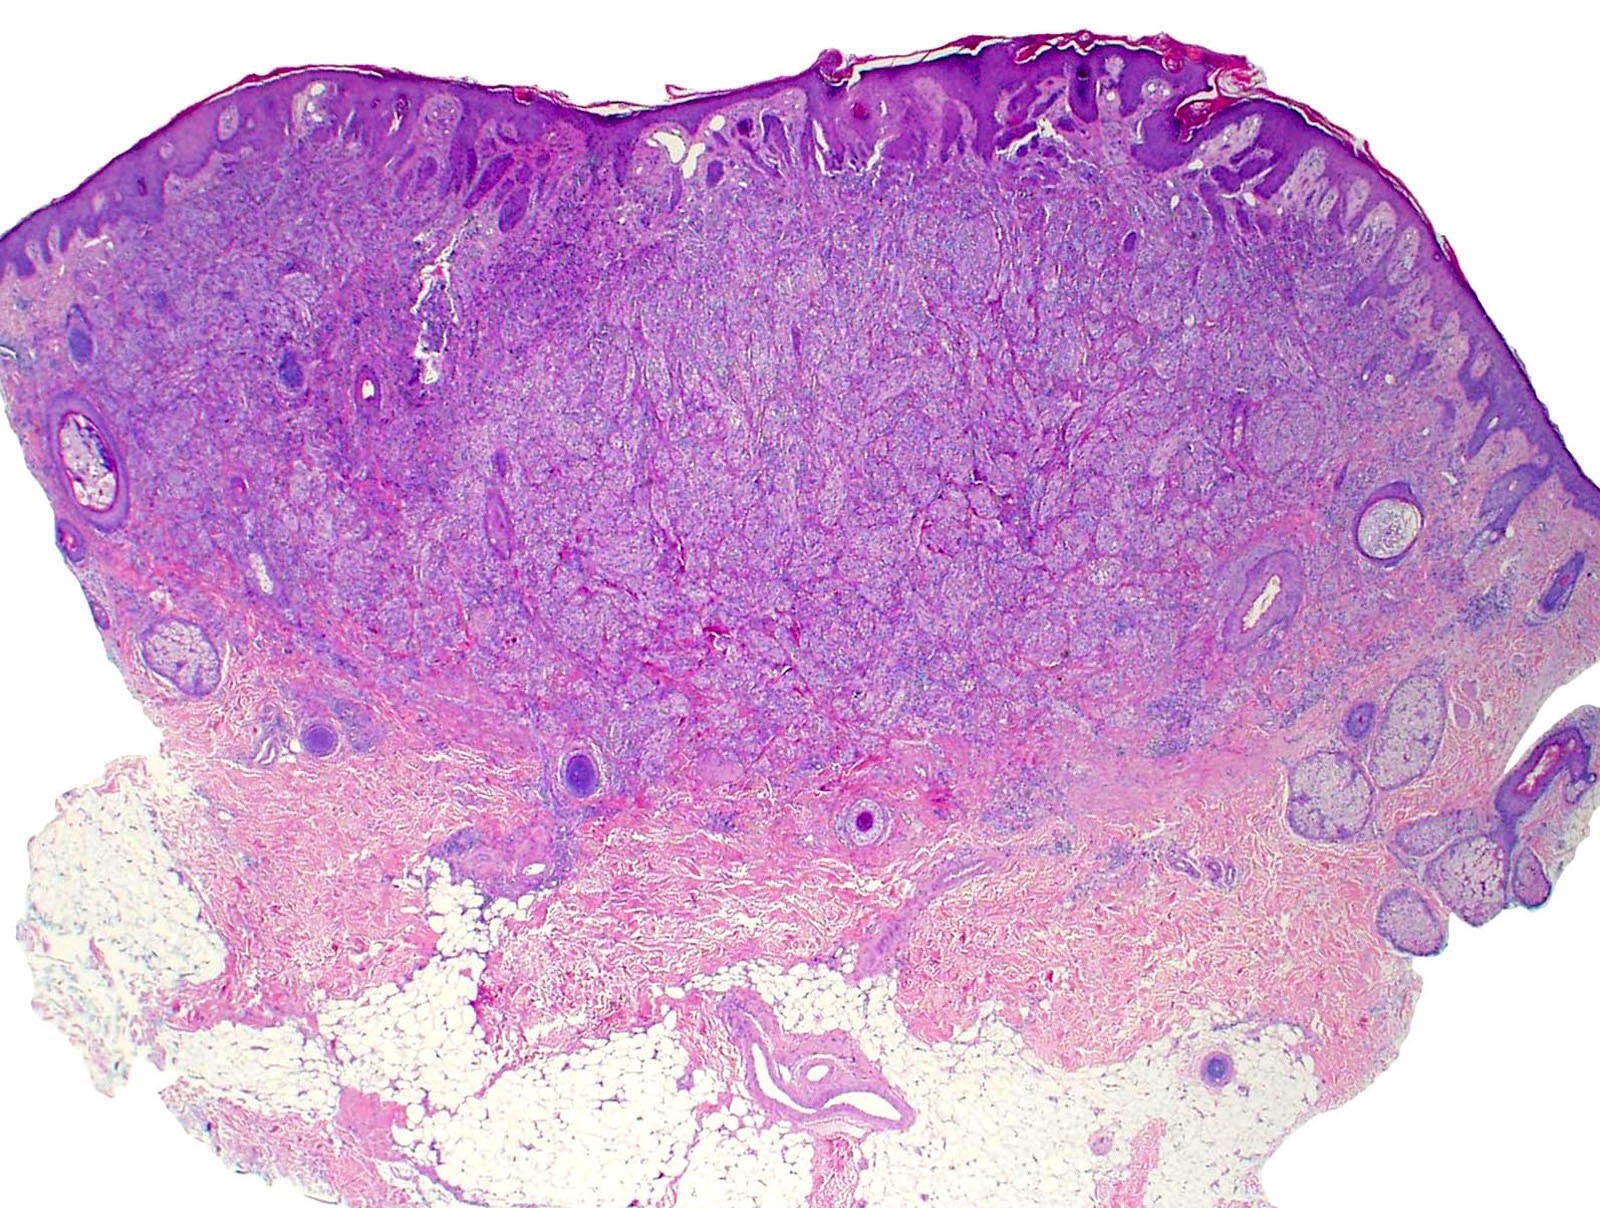

Microscopic (histologic) description

- Infiltrative or circumscribed architecture

- Can involve the subcutis

- Large polygonal cells with abundant eosinophilic granular cytoplasm and small, central nuclei

- Epidermis can show pseudocarcinomatous hyperplasia

- Lysosomal macroinclusions (pustulo-ovoid bodies of Milian) are usually present (J Cutan Pathol 2007;34:405)

- Can exhibit accentuation around arrector pili muscles or peripheral nerves (J Clin Pathol 2014;67:19)

- Nonneural granular cell tumors (S100-) can exhibit nucleomegaly, pleomorphism and variable mitotic activity (Am J Surg Pathol 1991;15:48, Histopathology 2005;47:179)

Microscopic (histologic) images

Contributed by Jarish Cohen, M.D., Ph.D.